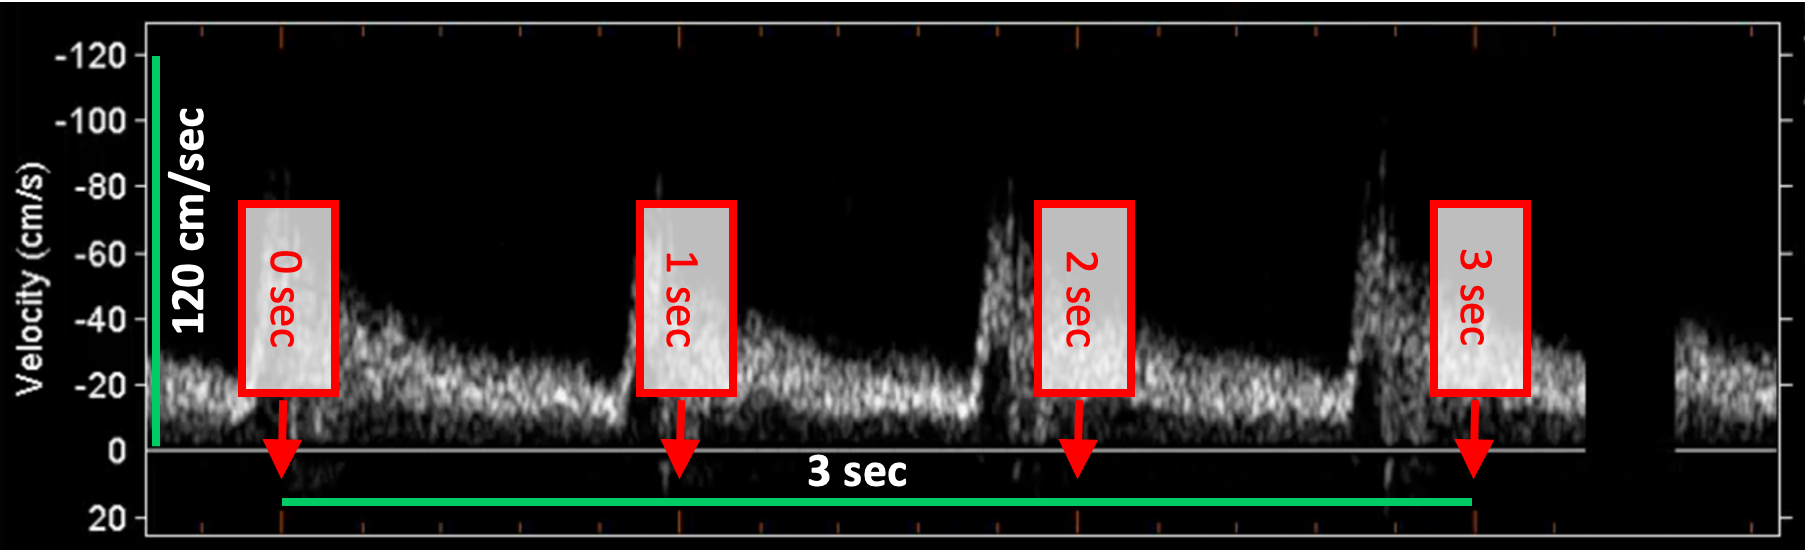

Doppler velocity calibration examples

The following images show examples of calibrations of the Doppler velocity image. Graphic items in red shows where you can find the information about the time scale in the ultrasound image.